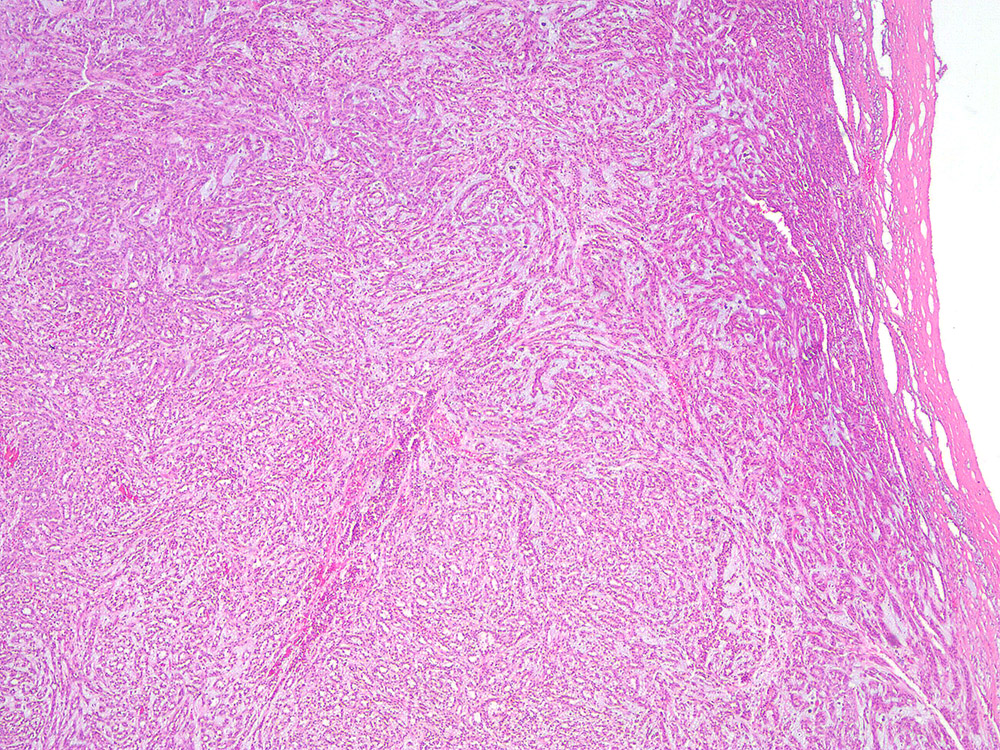

Consensus grade: Mucinous tubular and spindle cell carcinoma

Renal mass- 52 year old man